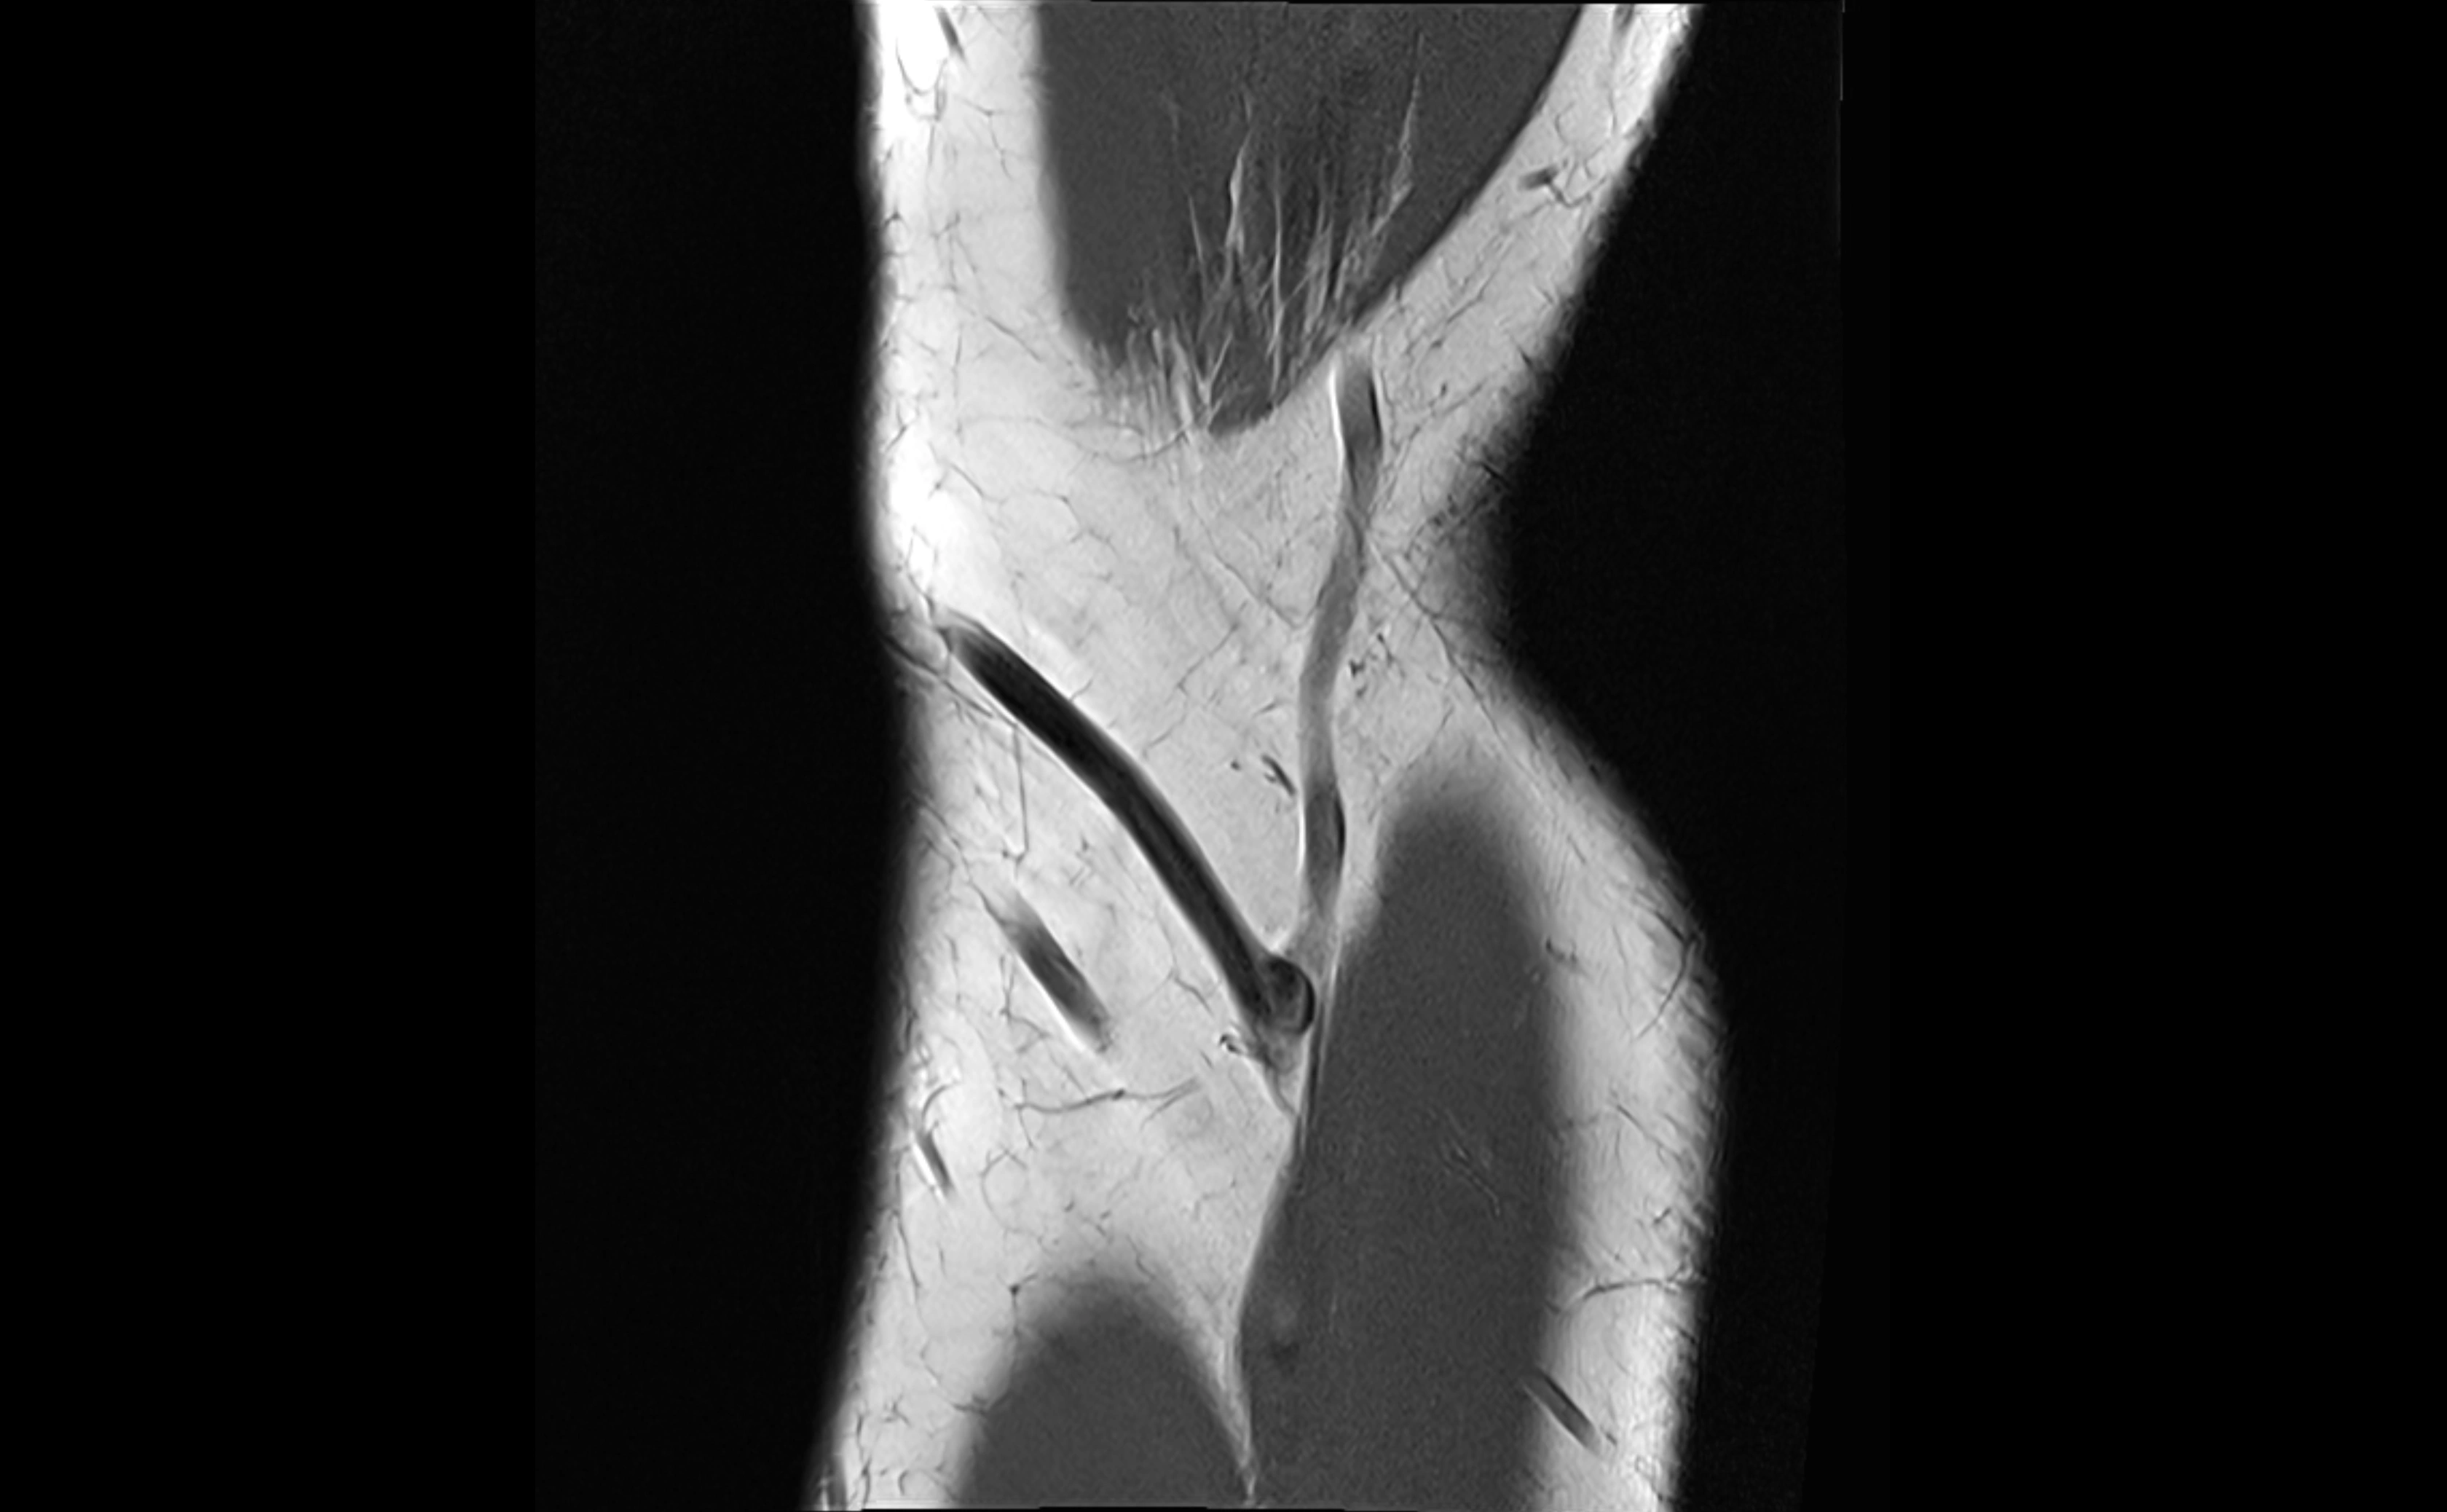

MRI Arthrogram Appearance

• Contrast outlines the proximal radioulnar joint and radial head recess.

• Normal ligament appears as a dark ring surrounding the radial head, containing the injected contrast within the joint cavity.

• Partial tear: contrast extends along the ligament or beneath its fibers.

• Complete tear or subluxation: contrast extravasates around the radial head or ulna, indicating discontinuity.

• Detects capsular defects, instability, or synovial invagination with high sensitivity.